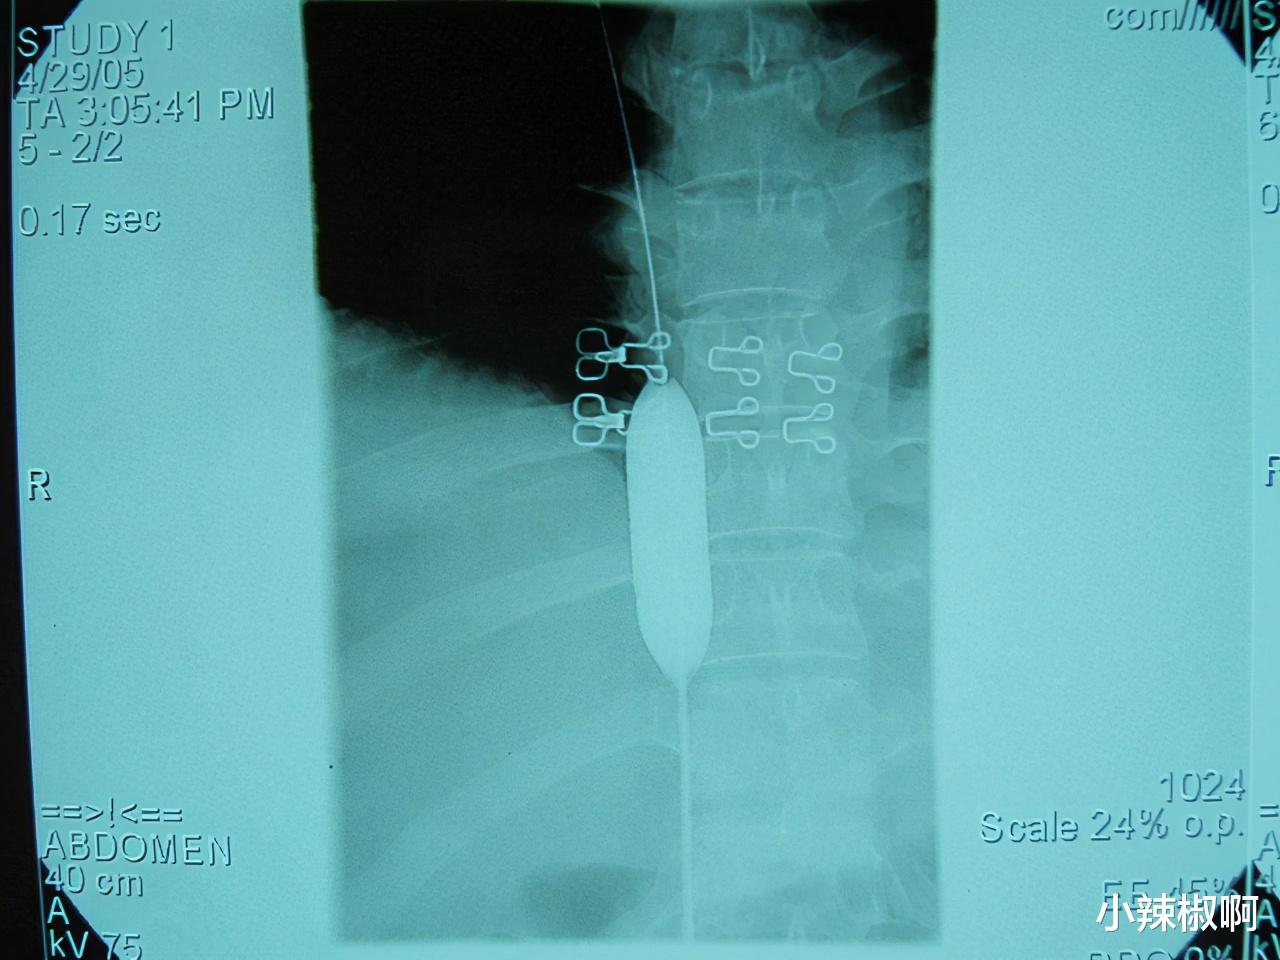

扩张狭窄处直到球囊上不再有压迹

狭窄改善 , 并且再次造影证实

治疗过程:初步诊断后第2天 , 进行穿刺右侧股静脉插管 , 下腔静脉造影 。 可见下腔静脉在第10胸椎上缘平面突然狭窄 , 呈现圆锥或称鸟嘴样表现 , 靠近心脏处呈一小孔状 , 造影剂如细线样喷射 , 其长度不足1厘米 。 又作侧位摄影 , 其形态与正位类似 。 还看到造影剂经过大量侧支循环回流到心脏 。 诊断为肝段下腔静脉膜性梗阻 , 布加综合征 , 田口(Tacheuchi)A型 。 确诊后立即采取介入微创治疗 。 经股静脉鞘放入硬导丝 , 操纵导丝进入狭窄段小孔 , 经右心房到达上腔静脉 。 经同轴导丝引入直径2厘米、长度4.5厘米的球囊 , 持续扩张狭窄处 , 直到球囊上不再有压迹 , 认为狭窄改善 , 并且再次造影证实 。 病人回病房后3小时即可下床适当活动 。 观察1天后无异常即出院 。 门诊随访5年无复发 。